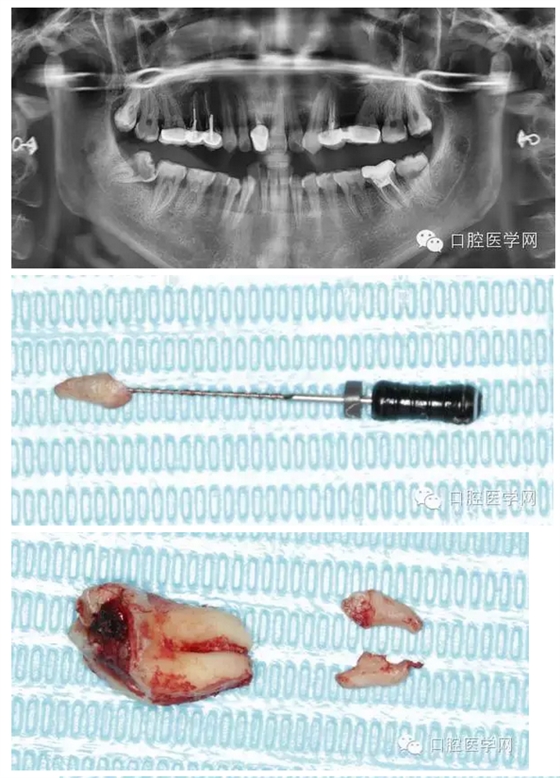

檢查發(fā)現(xiàn)右下8近中前傾阻生,合面大面積齲壞。拍全景片顯示右下8根尖向近中彎曲,右下7遠(yuǎn)中有淺齲,遠(yuǎn)中頸部有骨缺損。

拔牙過程就不贅述了,果然斷根了,于是用40號(hào)H銼插入牙根斷面的根管口里,并盡量擰緊,然后拔出。最近好像買不到碧藍(lán)麻,只有斯康杜尼,局部浸潤麻醉后出血明顯,嚴(yán)重影響操作,為了找根管口,擦拭了N個(gè)小棉球,讓人不堪忍受!讓人懷念的碧麻??!